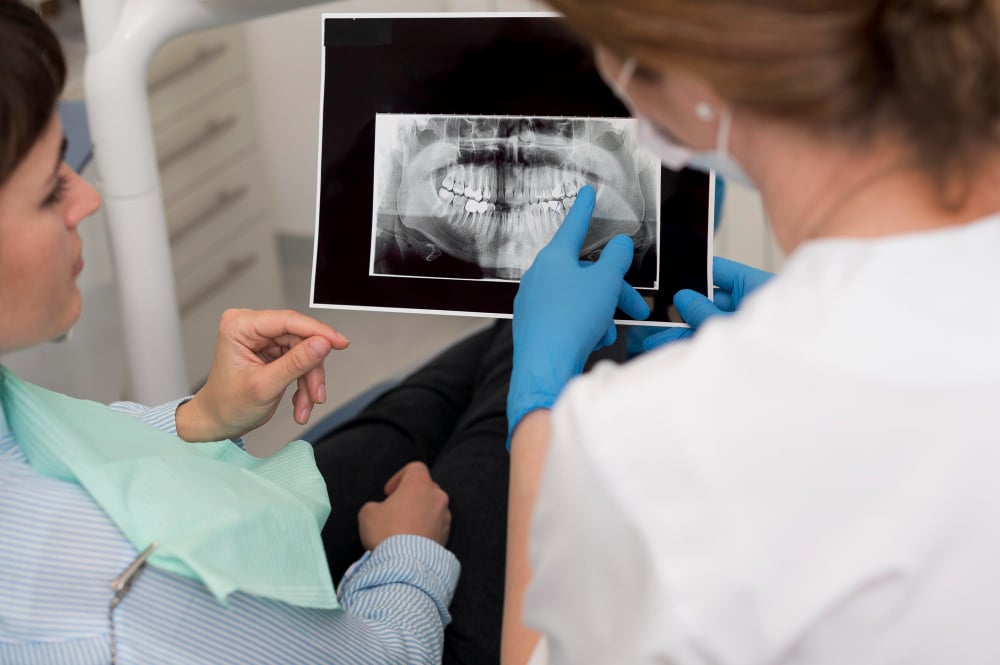

Every smile has a story, and our advanced dental photography helps us see yours in incredible detail. Using high-resolution imaging and advanced digital tools, we capture every detail of your teeth and gums, helping plan treatments with pinpoint accuracy. These images allow us to track progress, simulate outcomes, and make informed decisions tailored to your unique smile.

While the technology is next-level, our approach remains personal. We guide you through the process, explain the results, and ensure every image serves a clear purpose.

Dental photography is a specialised field that uses high-quality images to document, diagnose, plan, and communicate dental treatments. Unlike casual photos of a smile, dental photography requires precision, proper lighting, and specific angles to capture accurate representations of teeth, gums, and oral structures. These images serve as essential tools for both dentists and patients, ensuring treatments are planned and executed with precision.

We use dental photography to monitor your oral health over time. By comparing images from different appointments, we can track changes in tooth alignment, gum health, and the success of restorative or cosmetic treatments. This documentation is particularly important for complex procedures, such as veneers, implants, orthodontics, or full-mouth reconstructions.

Dental photography also enhances communication. Images help your dentist explain conditions and treatment options clearly, giving you a visual understanding of your dental health. They also allow collaboration with specialists, ensuring every aspect of your treatment plan is coordinated and precise.